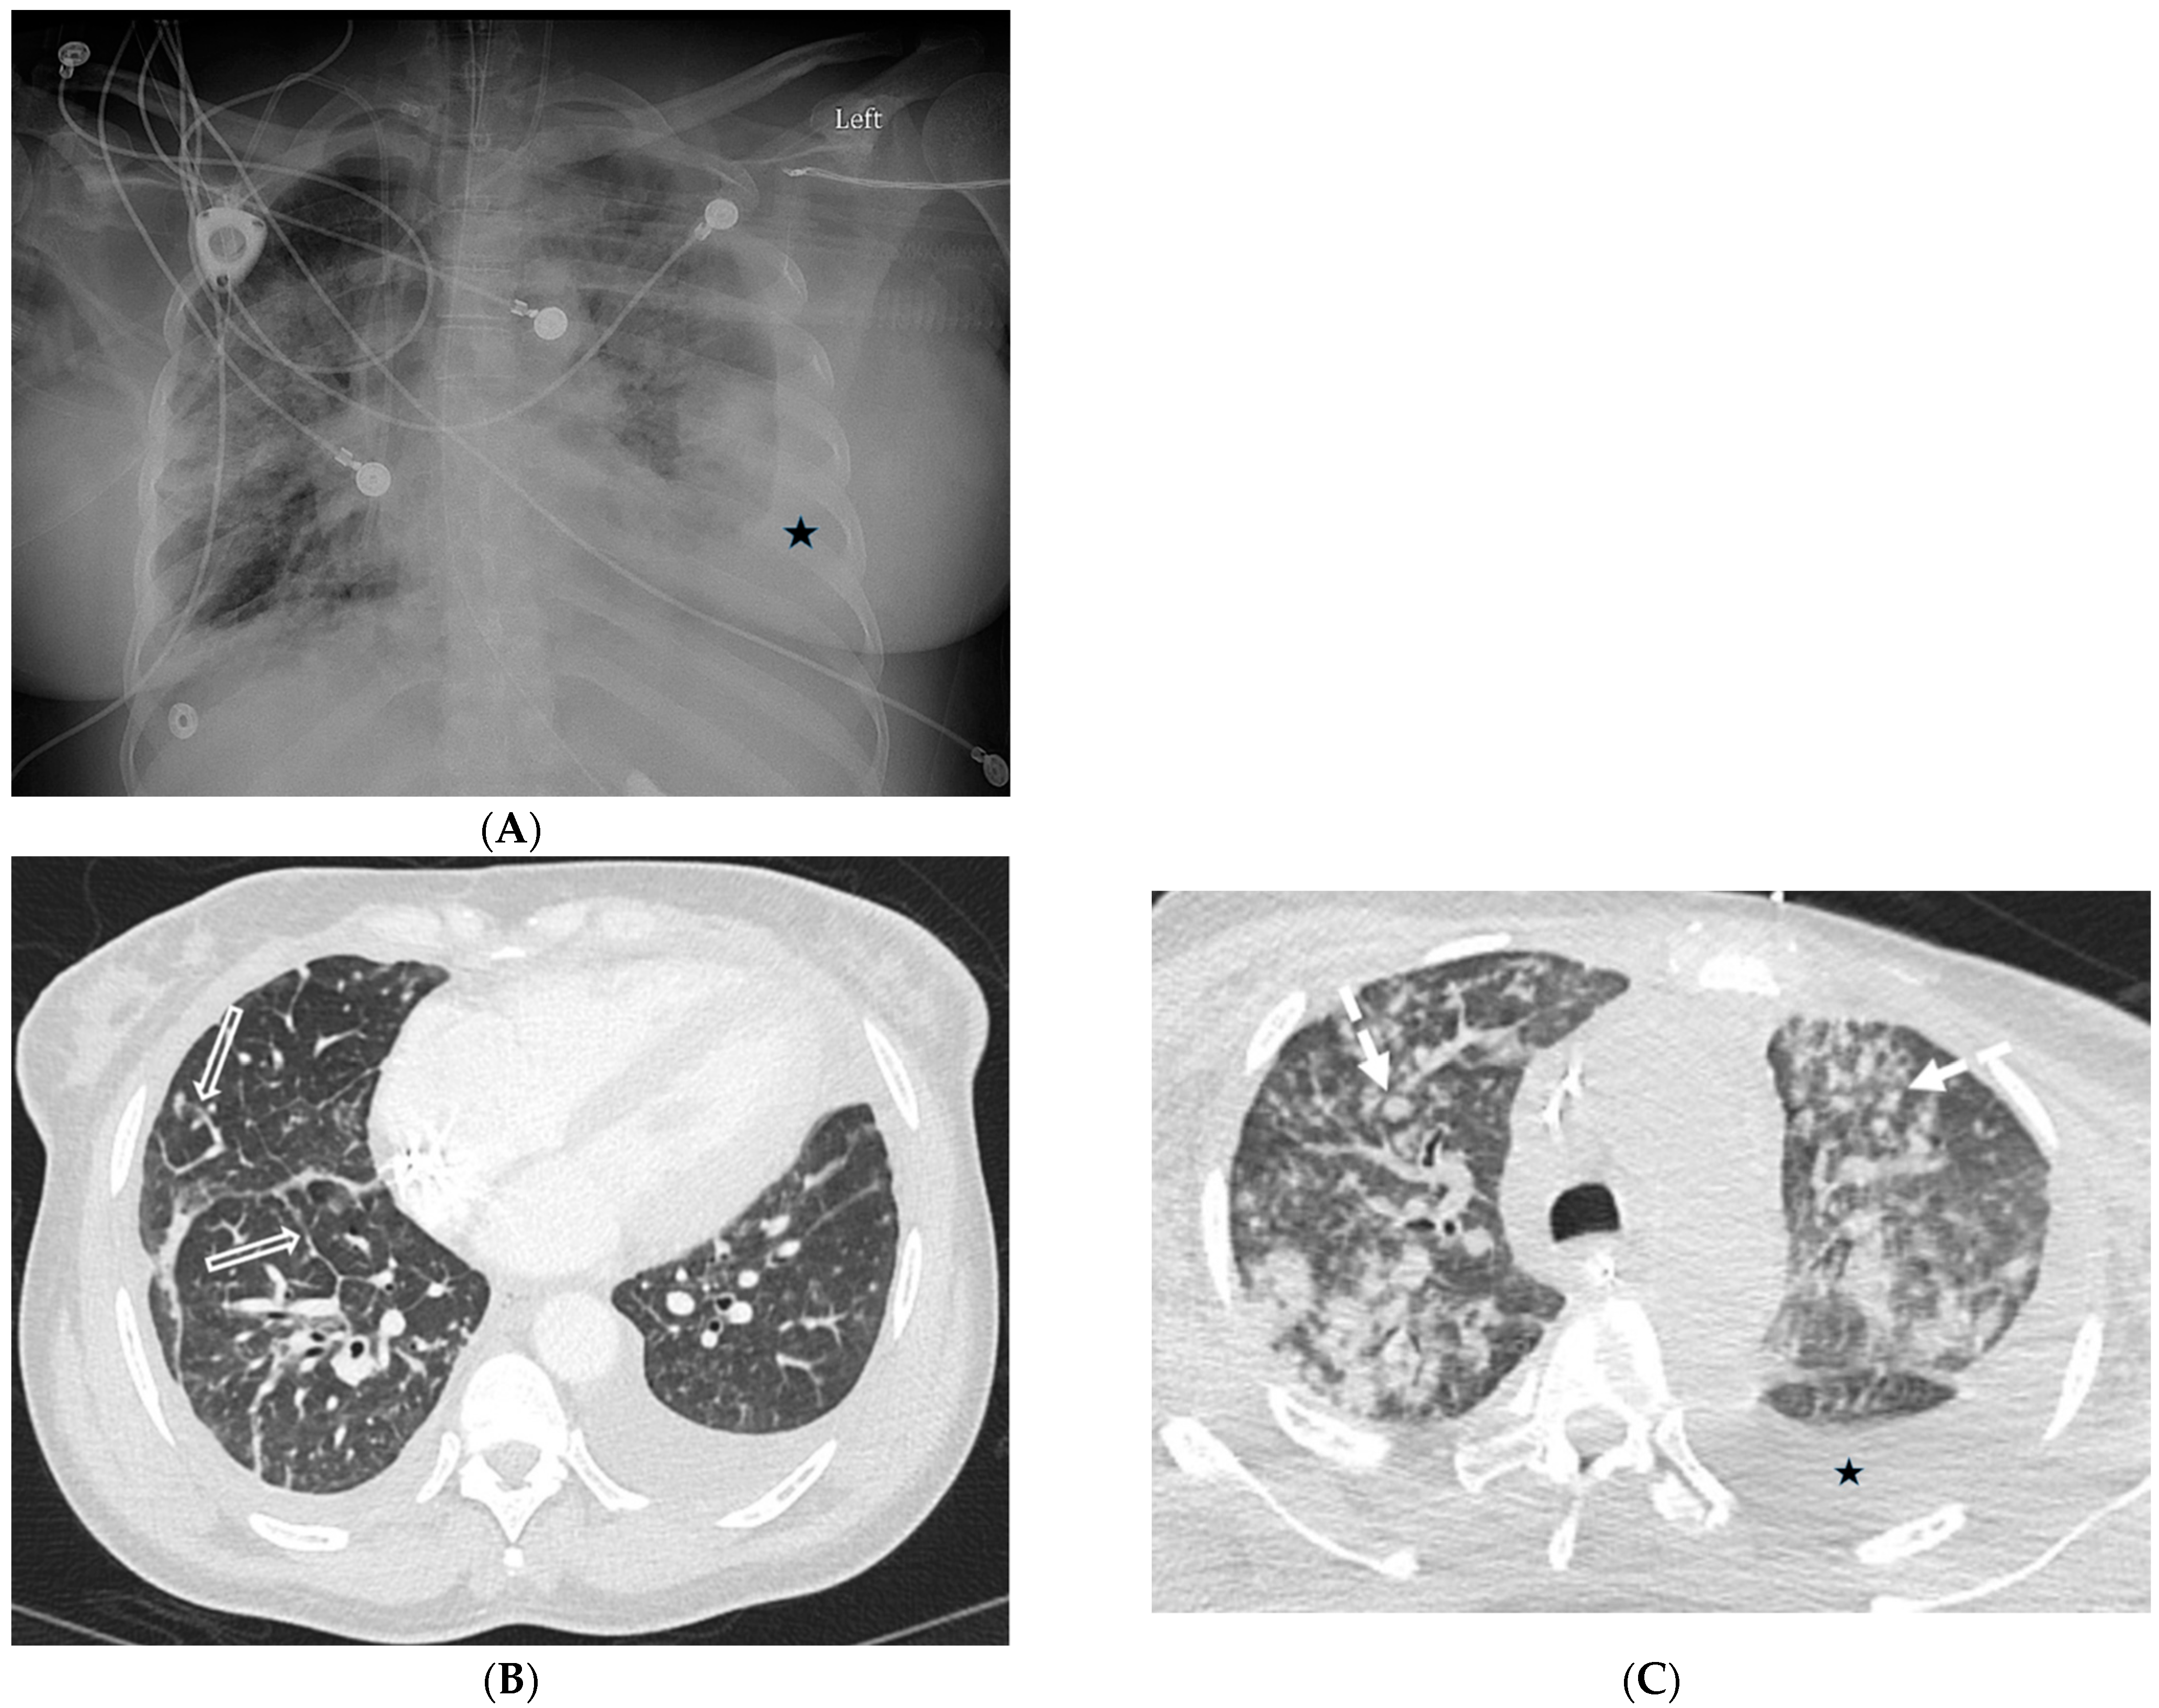

8.2. Granulomatous–Lymphocytic Interstitial Lung Disease (GLILD)

- Torigian, D.A.; LaRosa, D.F.; Levinson, A.I.; Litzky, L.A.; Miller, W.T., Jr. Granulomatous-lymphocytic interstitial lung disease associated with common variable immunodeficiency: CT findings. J. Thorac. Imaging 2008, 23, 162–169. [Google Scholar] [CrossRef]